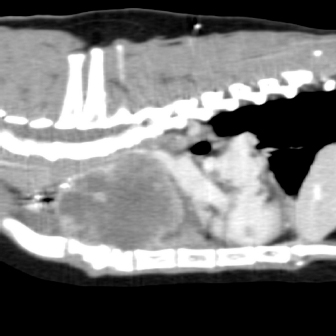

On physical examination, the cat had an unkept coat, reduced respiratory sounds cranially, and persistent stridor, but was otherwise bright and ambulatory. Computed tomography (CT) was performed using a Phillips Brilliance six slice CT. Multiphase contrast-enhanced CT images of the head, thorax, and abdomen were acquired with the cat in sternal recumbency (Figs. 1 and 2). A cranial mediastinal mass measuring 60 × 40 mm causing dorsal tracheal displacement toward the right was identified. With contrast administration, there was moderate enhancement of the periphery (+60 Hu) and poor central enhancement (+10 Hu). There was moderate to marked compression of the cranial vena cava, with a focal intraluminal contrast-filling defect at the cranial aspect of the vena cava just caudal to the mass. Here, the path of the cranial vena cava could not be completely traced, suggesting almost complete compression or invasion. There was no evidence of subcutaneous edema of the head or cervical region. Moderate volume of pleural fluid was bilaterally present. Multifocal, slightly branching soft tissue conglomerates largely following the bronchi of the caudal lobes toward the apex was noted, most likely to be bronchial disease with bronchiolar consolidation. Pulmonary metastatic neoplasia was considered to be unlikely. Surgical resection in the form of debulking was recommended on the basis that the large cranial mediastinal mass was most likely the cause of the cat’s clinical signs, and that reduction of gross disease should improve survival time as well as being more responsive to adjunctive treatment with chemotherapy. The cat was then started on mirtazapine (1.875 mg orally every 48 hours) and prednisolone (5 mg orally every 24 hours).

Fig. 1. Computerized tomography of the cranial mediastinal mass (sagittal plane).

Fig. 2. Computerized tomography of the cranial mediastinal mass (coronal plane).